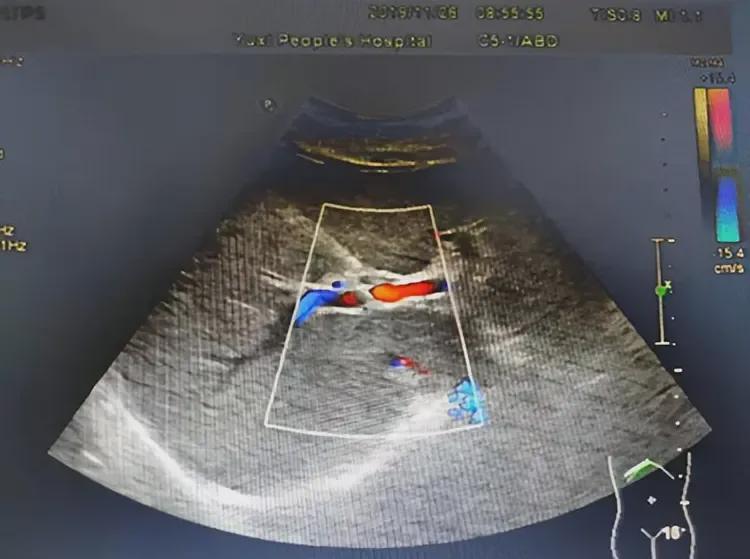

检查结果显示:叶阿姨左附件区有一个小囊肿,约2.7×2.4CM囊性回声,盆腔还有少量积液。一听“囊性回声”,叶阿姨立刻联想到监听器,认为那就是医生安装的“证据”。

法官也觉得此事颇为奇葩,于是又将叶阿姨送到另一间医院进行检查。检查结果显示,她的子宫内并没有“监听器”等异物,只有“囊性回声”存在。

然而,叶阿姨却坚持认为囊性回声就是“监听器”。法官在啼笑皆非之余,驳回了叶阿姨的赔偿诉求。

其实,从普通的科学常识就可以判断,医生在子宫内安装监听器是无稽之谈。子宫内环境潮湿、缺氧、含腐蚀性体液,电子设备无法长期工作。此外,医用植入设备需体外充电或定期更换,无法隐匿近十年。而且,彩超对金属异物敏感度高,若有监听器必然会被发现。

因此,叶阿姨所述的“监听器”实为卵巢囊肿(囊性回声),属常见良性病变,可能引发腹痛。叶阿姨用手机播放歌曲时偶尔与腹痛巧合,于是形成了“被监听”的幻想,这属于被害妄想症或躯体化障碍。